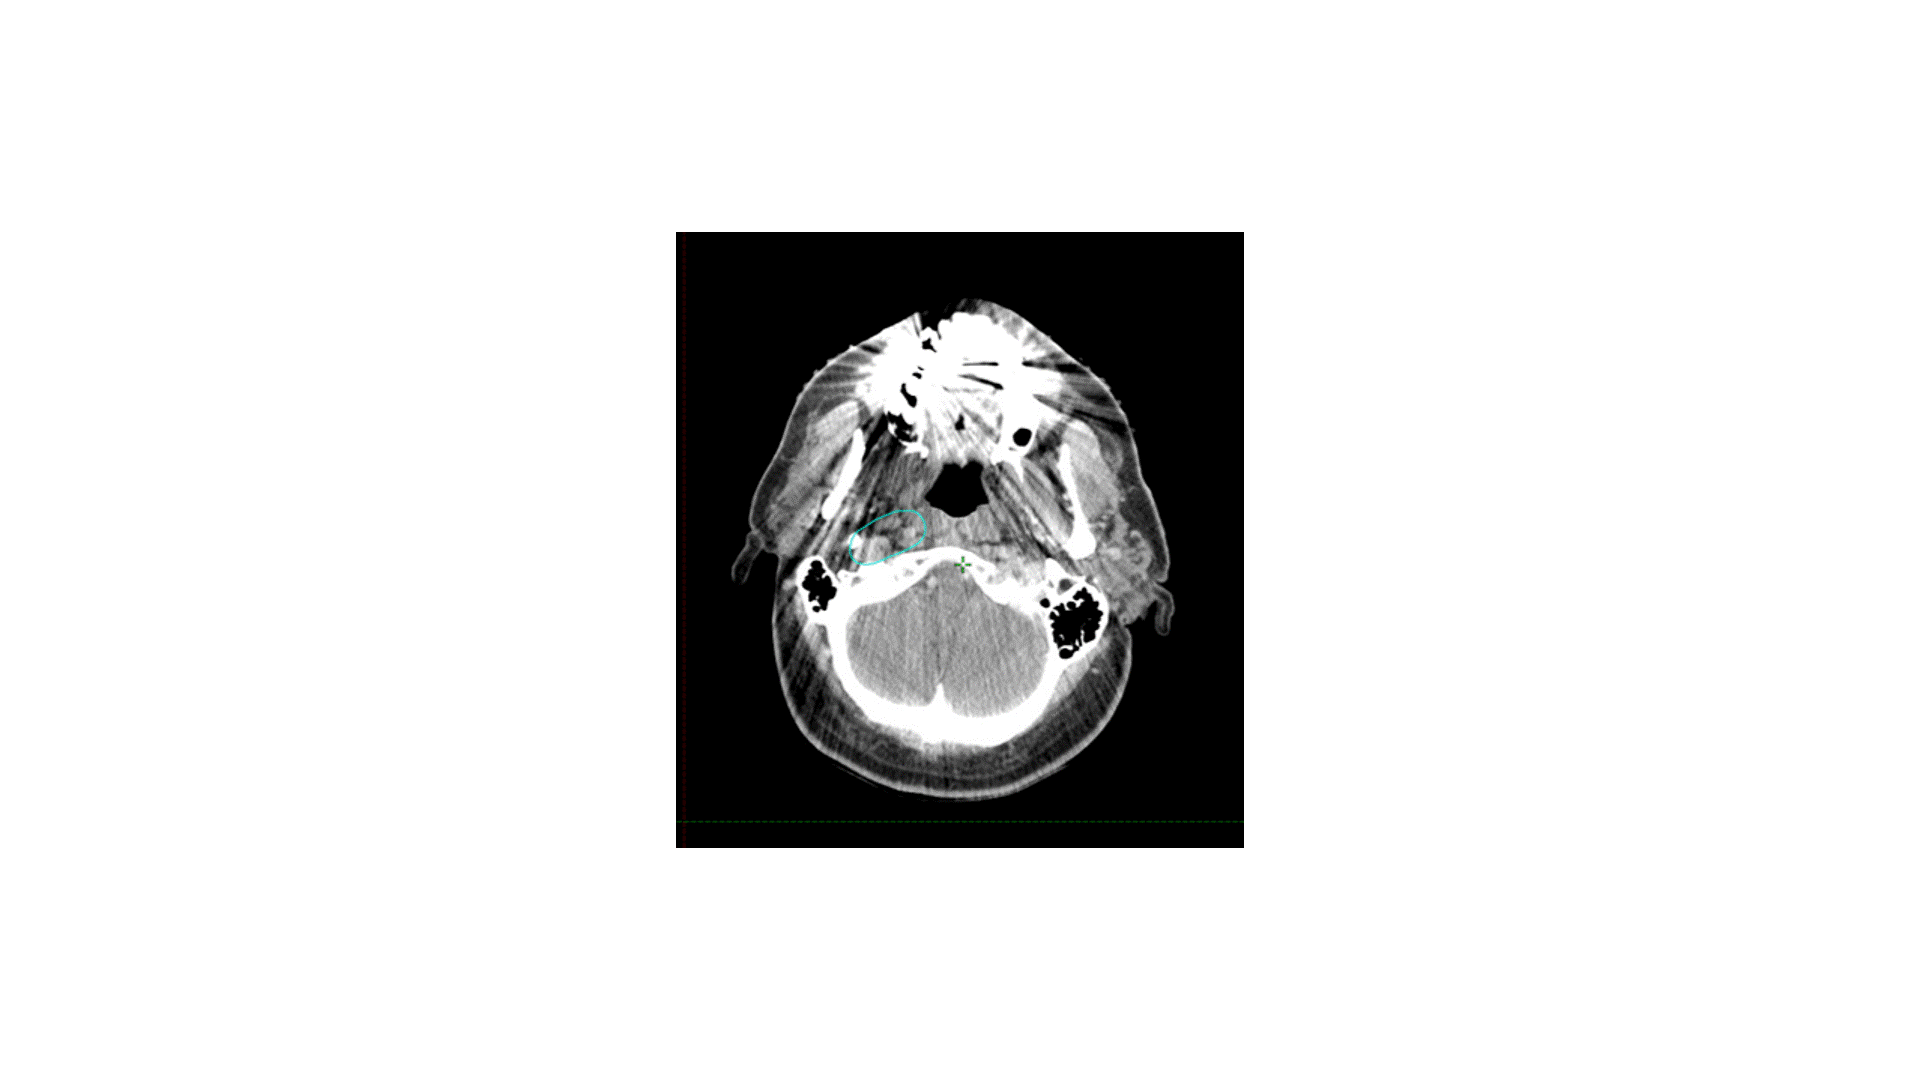

The indication for adjuvant radiation in this case was a lymph node > 3 cm. The primary was T2 without PNI or LVSI and 3 mm margins, so I did not specifically target the primary, though I did include some clips. The treatment I chose for this patient was option B, treating the right level II-V (56 Gy) plus the retrostyloid and lateral retropharyngeal lymph nodes (50 Gy). Chemotherapy was not indicated. Simply treating II-V would not have been adequate, as oropharyngeal primaries do drain to the retropharyngeal lymph nodes, and failure there can be catastrophic. Furthermore, with a 4 cm ipsilateral lymph node in level II, there is risk of retrograde drainage to the retropharyngeal region.

How I do it: defining retropharyngeal nodes at risk

Remember that there are lateral and medial retropharyngeal lymph nodes (RPLNs). When there is pathologic involvement of RPLNs, it is almost always the lateral RPLN that is involved first. Note that the lateral RPLN space is the fat space (dark on CT) immediately medial to the internal carotid artery.

When electively treating the retrostyloid and RPLN as in this case, I usually only treat the lateral RPLN. If the RPLN was grossly involved with cancer, I would include both the lateral and medial RPLNs.